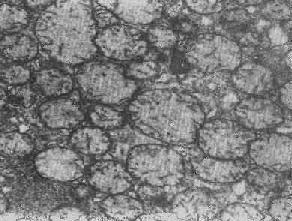

四、线粒体线粒体(mitochondrion)是细胞内主要的能量形成所在,故不论在生理上或病理上都具有十分重要的意义。 线粒体为线状、长杆状、卵圆形或圆形小体,外被双层界膜。外界膜平滑,内界膜则折成长短不等的嵴并附有基粒。内外界膜之间为线粒体的外室,与嵴内隙相连,内界膜内侧为内室(基质室)(图1-8)。在合成甾类激素的内分泌细胞(如肾上腺皮质细胞、卵甾滤泡细胞、睾丸的Leydig细胞等),线粒体嵴呈小管状。内外界膜的通透性不同,外界膜的通透性高,可容许多种物质通过,而内界膜则构成明显的通透屏障,使一些物质如蔗糖和NADH全然不能通过,而其他物质如Na+ 和Ca 2+等也只有借助于主动运输才能通过。线粒体的基质含有电子致密的无结构颗粒(基质颗粒),与二价阳离子如Ca2+及Mg2+具有高度亲和力。基质中进行着β氧化、氧化脱羧、枸橼酸循环以及尿素循环等过程。在线粒体的外界膜内含有单胺氧化酶以及糖和脂质代谢的各种转移酶;在内界膜上则为呼吸链和氧化磷酸化的酶类。 线粒体是对各种损伤最为敏感的细胞器之一。在细胞损伤时最常见的病理改变可概括为线粒体数量、大小和结构的改变: 1.数量的改变 线粒体的平均寿命约为10天。衰亡的线粒体可通过保留的线粒体直接分裂为二予以补充。在病理状态下,线粒体的增生实际上是对慢性非特异性细胞损伤的适应性反应或细胞功能升高的表现。例如心瓣膜病时的心肌线粒体、周围血液循环障碍伴间歇性跛行时的骨骼肌线粒体的呈增生现象。 线粒体数量减少则见于急性细胞损伤时线粒体崩解或自溶的情况下,持续约15分钟。慢性损伤时由于线粒体逐渐增生,故一般不见线粒体减少(甚至反而增多)。此外,线粒体的减少也是细胞未成熟和(或)去分化的表现。 2.大小改变 细胞损伤时最常见的改变为线粒体肿大。根据线粒体的受累部位可分为基质型肿胀和嵴型肿胀二种类型,而以前者为常见。基质型肿胀时线粒体变大变圆,基质变浅、嵴变短变少甚至消失(图1-9)。在极度肿胀时,线粒体可转化为小空泡状结构(图1-10,图1-11)。此型肿胀为细胞水肿的部分改变。光学显微镜下所谓的浊肿细胞中所见的细颗粒即肿大的线粒体。嵴型肿较少见,此时的肿胀局限于嵴内隙,使扁平的嵴变成烧瓶状乃至空泡状,而基质则更显得致密。嵴型肿胀一般为可复性,但当膜的损伤加重时,可经过混合型而过渡为基质型。 线粒体为对损伤极为敏感的细胞器,其肿胀可由多种损伤因子引起,其中最常见的为缺氧;此外,微生物毒素、各种毒物、射线以及渗透压改变等亦可引起。但轻度肿大有时可能为其功能升高的表现,较明显的肿胀则恒为细胞受损的表现。但只要损伤不过重、损伤因子的作用不过长,肿胀仍可恢复。 线粒体的增大有时是器官功能负荷增加引起的适应性肥大,此时线粒体的数量也常增多,例如见于器官肥大时。反之,器官萎缩时,线粒体则缩小、变少。

图1-8 心肌细胞线粒体